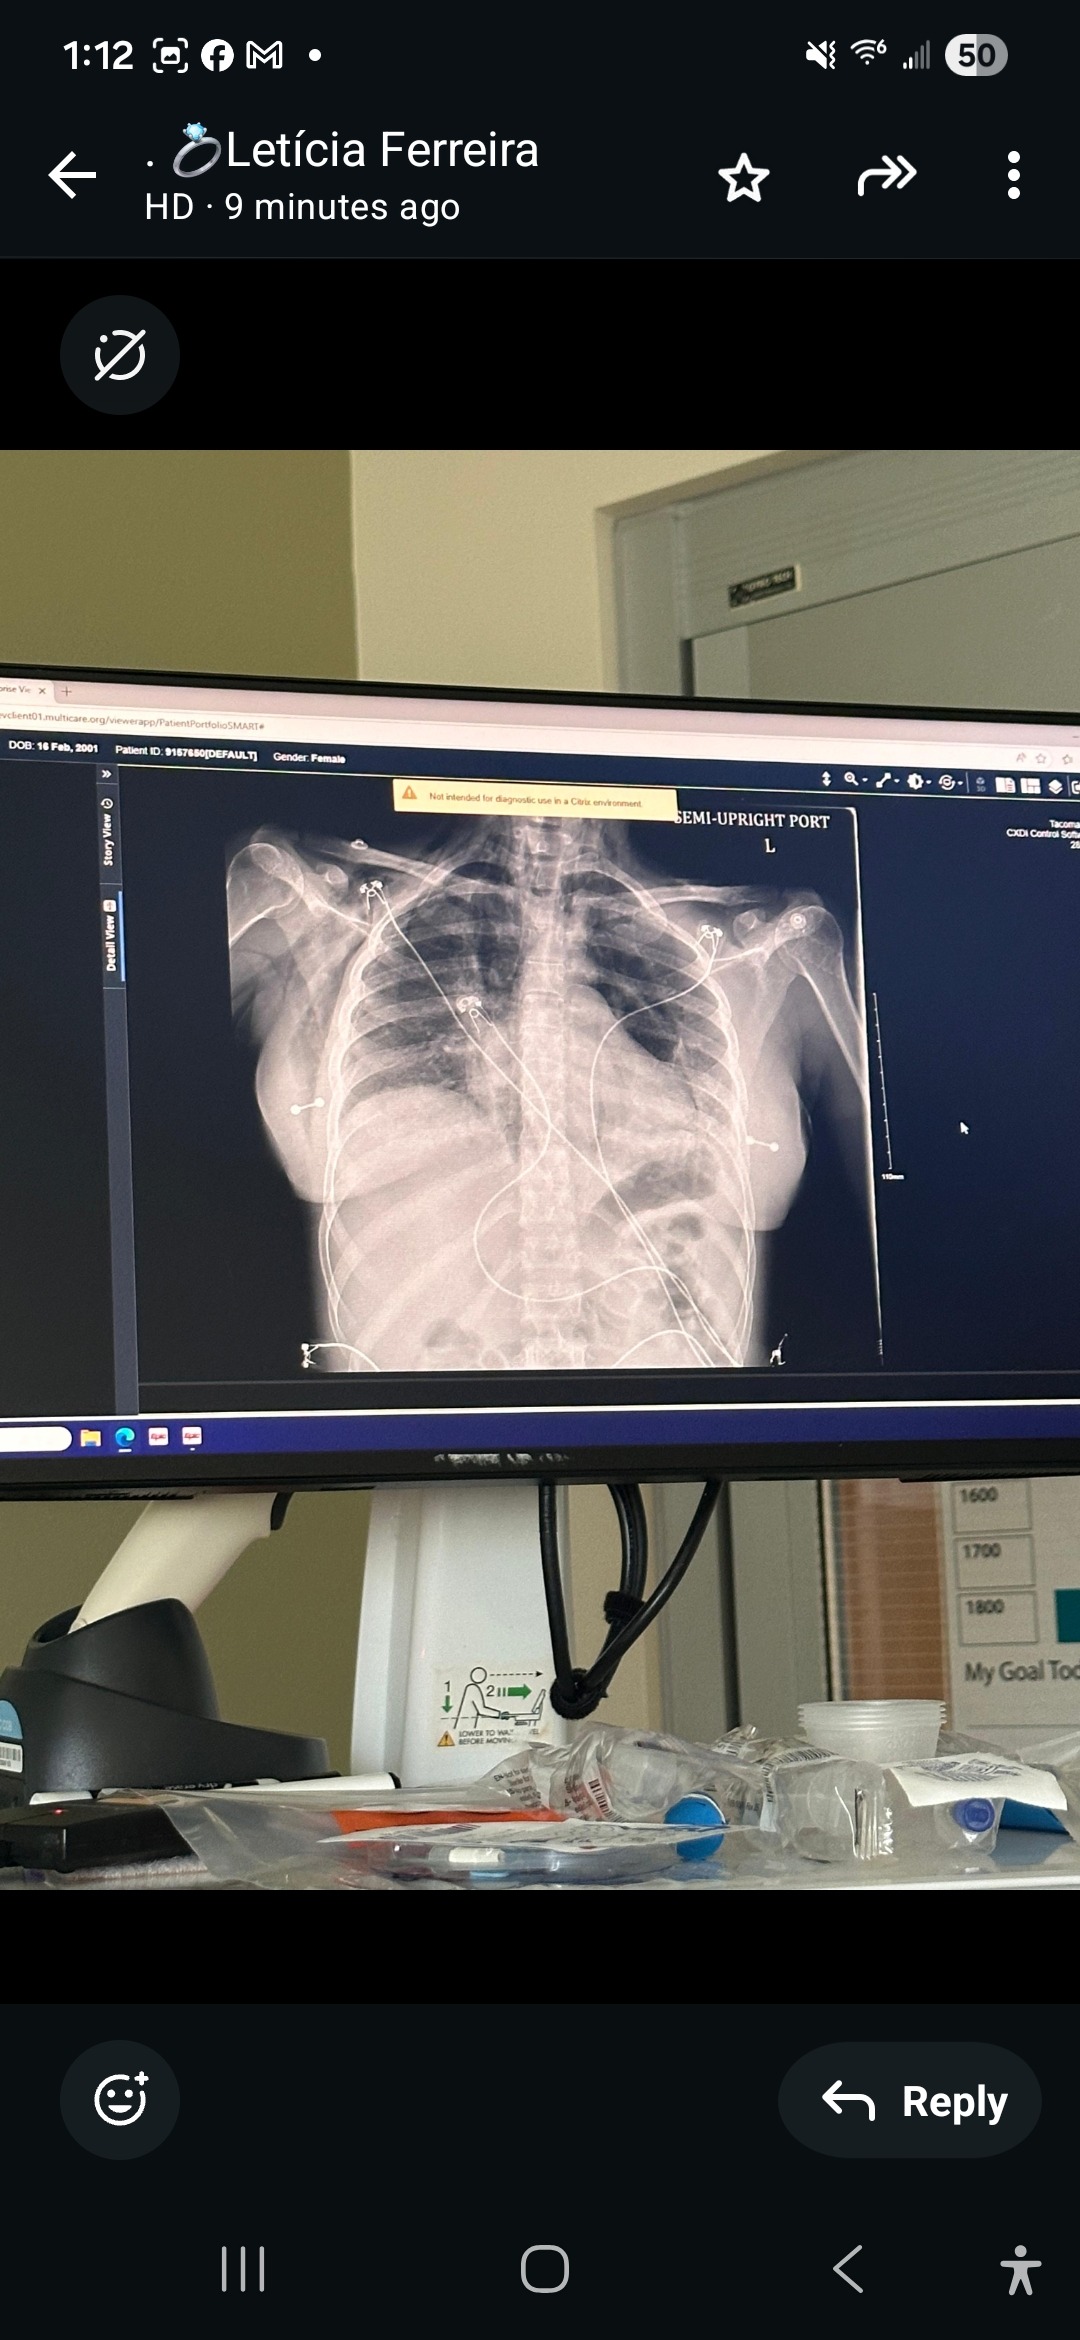

My wife is Suffering from critical lung failure and fighting for her life at Harborview Medical in Seattle WA. Doctors have been unable to definitively identify a clear cause of her illness and do not have a cure. She is being kept alive by a machine called ECMO, which temporarily replaces the function of her lungs.

On January 21, 2026, doctors placed her on ECMO after her lungs could no longer support her on their own. ECMO carries an estimated 50% mortality rate, and she may still require a lung transplant.